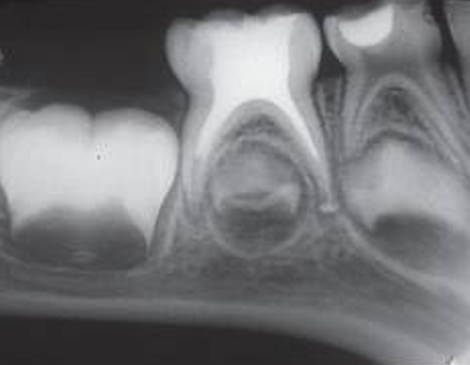

root canal endodontic treatment root canal endodontic treatment root canal endodontic treatment